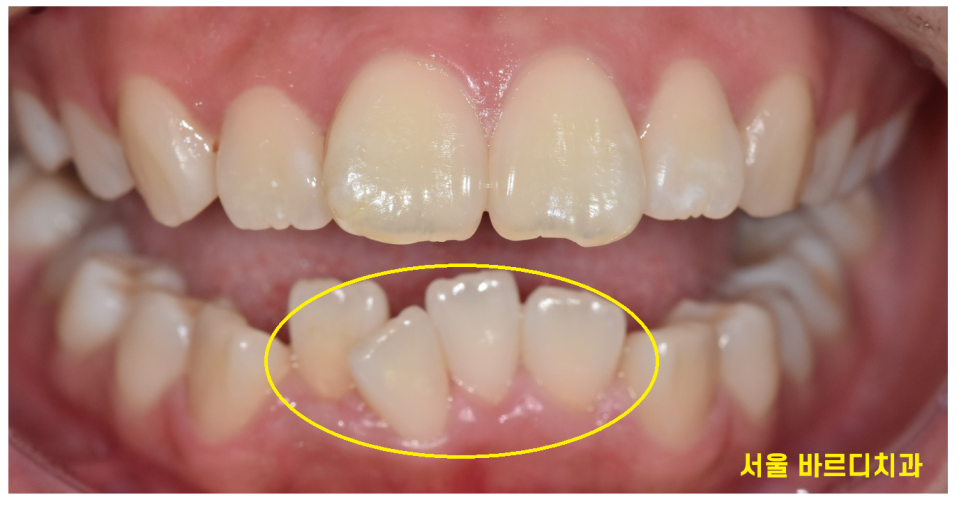

1)공간 부족

삐뚤 빼뚤한 배열을 개선하고 싶은데

치아 공간이 부족한거죠~

공간이 부족하여 제 위치를 벗어나 올라오는 덧니가 있을 수도 있고요~

요즘 아이들은 턱이 워낙 좁아 치열 자체가 좁기도합니다.